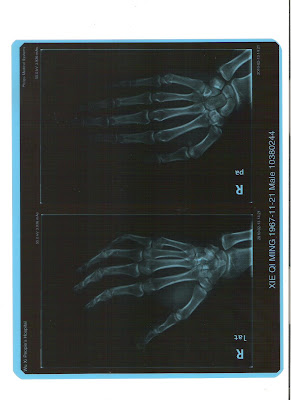

(爱克斯光片显示谢其明遭到北京安元鼎保安公司人员暴力后的手指骨折)

1月30日晚,我们一行18人被押上北京安元鼎保安公司的大客车,押送回无锡,随行有20多个保安,每个保安看管一人,我们相互之间被禁止说话,一人说话就被几个看押人员恐吓、谩骂。晚上车行至河北沧州高速公路休息站时,因多个保安在车内吸烟,我们18人中16个是妇女,她们已被呛得剧烈咳嗽,呼吸困难,要求保安不要再吸烟,但立即遭他们的谩骂,其中一个领队的胖子,身材非常高大壮实,动手殴打了妇女沈建群,前座的妇女王品仙责问那“胖子”为什么打人,没想到“胖子”转身就对王品仙劈头盖脸地一阵猛打,嘴里还不停地狂叫:“我让你们知道什么叫打人!”王品仙的脸上立即被打得破皮流血,眼眶乌黑,“胖子”不光在王品仙的头脸上狠打,见她年轻貌美,还对她胸部乱打乱抓,这发生在众目睽睽之下的恶行暴行,连随行的部分男女保安都看不过,也喊“胖子”不要打了。但“胖子”不听,继续欧打王品仙。这时无锡的谢其明上好厕所刚回到车上,见“胖子”殴打王品仙,对“胖子”说:“有事好好说,你不能打人啊。”“胖子”不说话回手就对谢其明脸上打了几拳,还叫其他2个保安一起欧打谢其明。后来在回途中“胖子”继续单独和带领其他保安对王品仙和谢其明暴力殴打,在车上继续对王品仙殴打了一次,对谢其明在车上继续殴打了2次,在车下又殴打了一次,致使谢其明右手指骨折(见医院诊断报告),造成永久伤害,他们2人当时伤痕累累,脸部乌青流血破相,以上事实由我们18人和车上20多个男女保安全程见证。